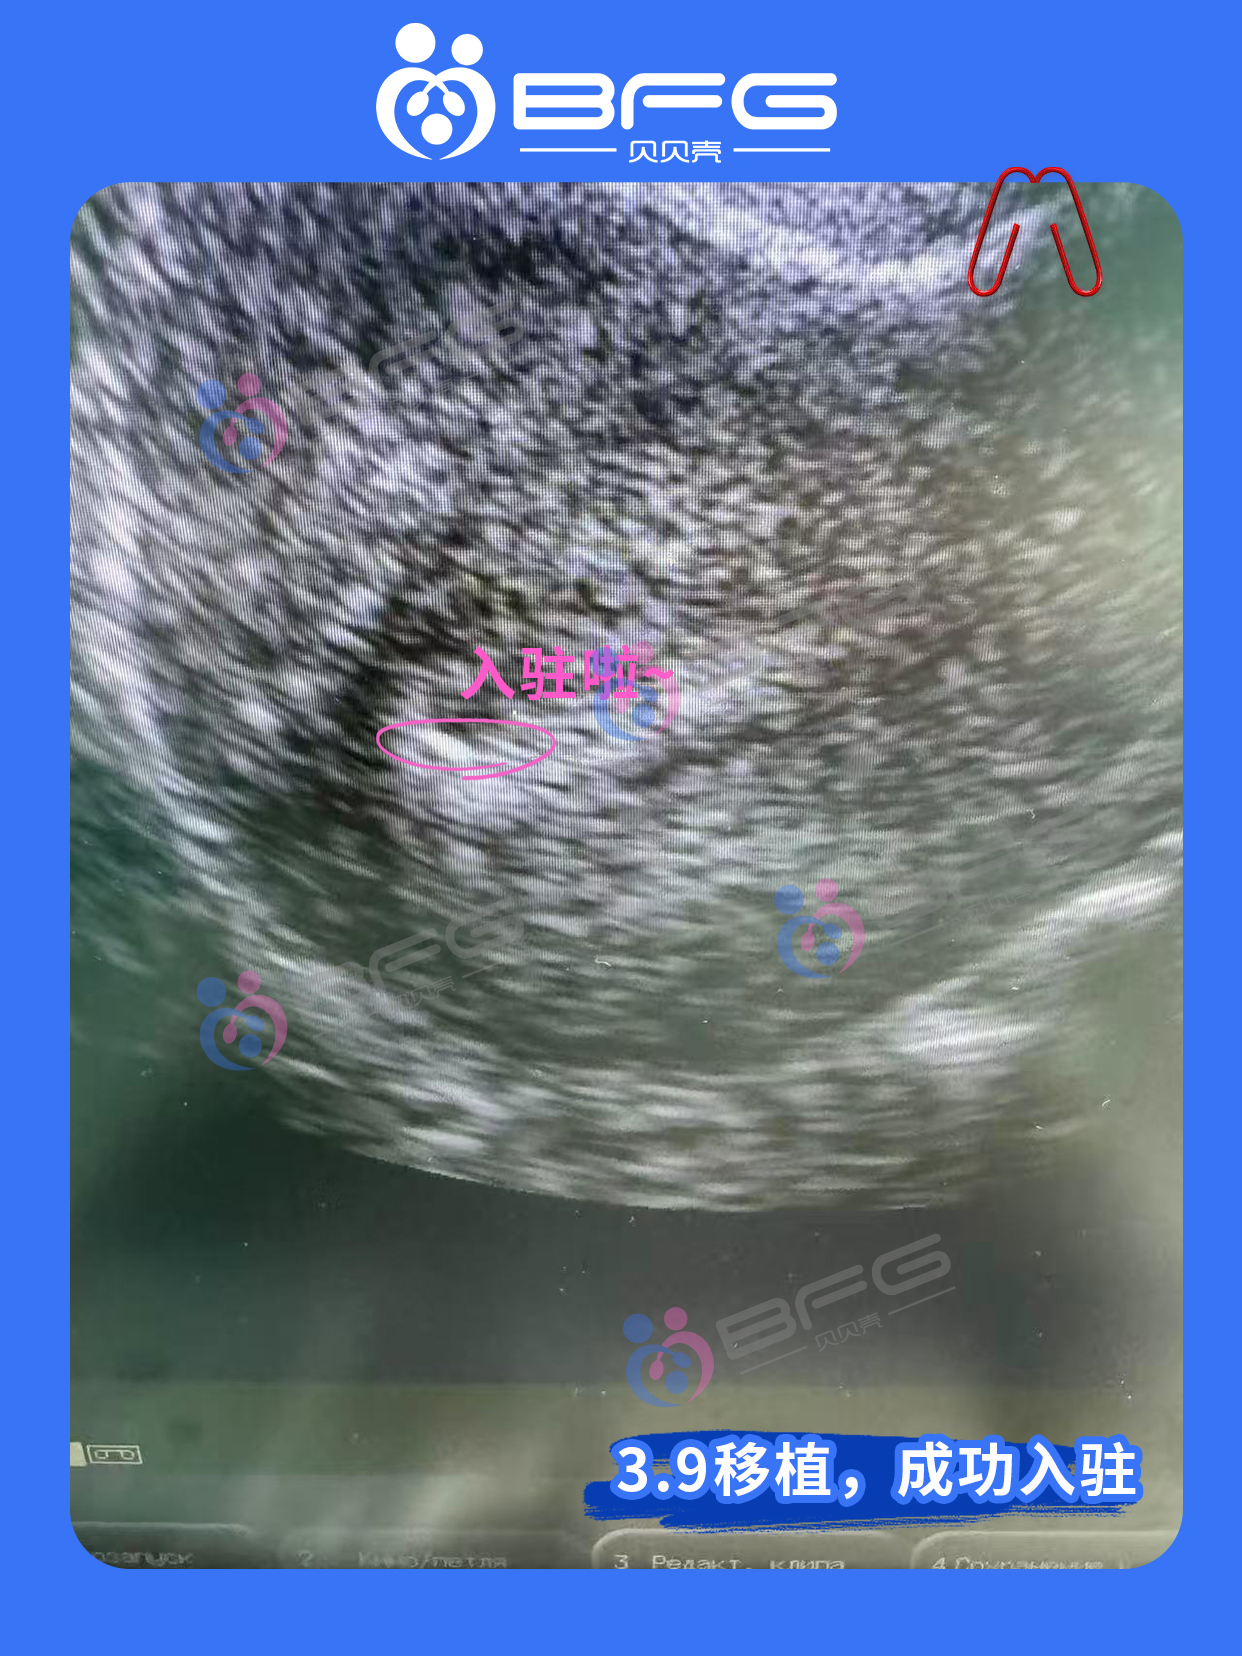

[爱心]妈妈好孕时间线:3.8移植前叮嘱&签字→3.9移植→3.16移植7天后测hcg 53.8,成功着床。愿孕程如春光明媚,宝宝健康发育,期待拥抱你的那一天!